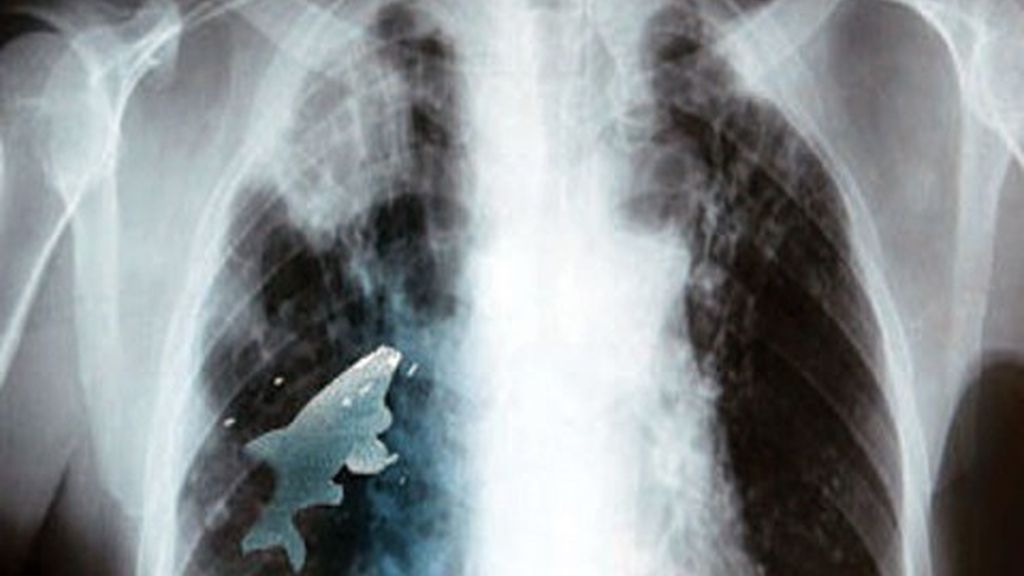

Extraen un pez vivo del pulmón de un niño

Esto de jugar a tragarse un pez era un pasatiempo usual de Anil y sus amigos, que pasaban buenos ratos en el río del vecindario, pero esta vez el pez no fue al estómago, sino que lo aspiró y terminó en su pulmón izquierdo a través de la tráquea, según publicó The Nation, un periódico de Pakistán.

Anil fue sometido a una intervención quirúrgica de urgencia que duró 45 minutos y que lo salvó. El pez estaba vivo cuando los cirujanos llegaron a él a través de la broncoscopía.